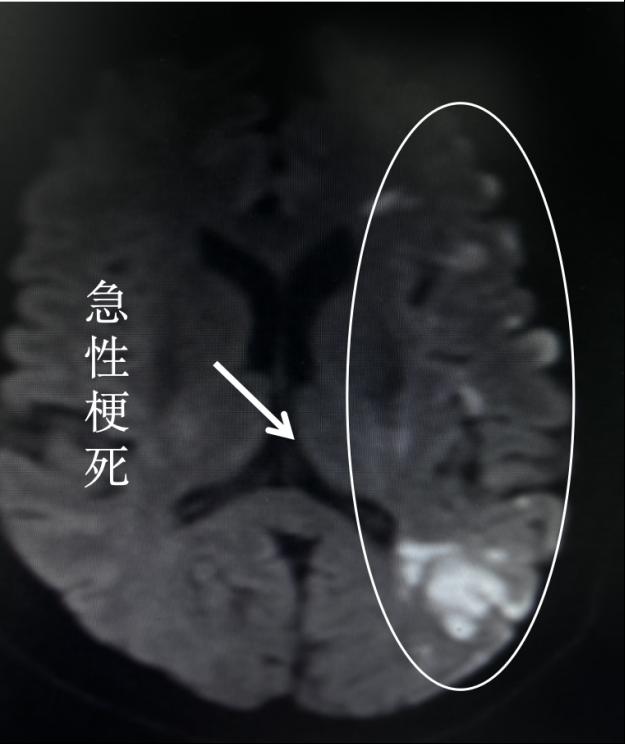

据了解,患者睡觉时被朋友发现异常送来医院就诊。医院立即开启绿色通道,核磁共振检查发现脑梗死病灶,患者大血管闭塞,需要急诊开通脑血管。由于患者非常年轻,父母都已去世,孩子还小,妻子联系不到,耽误的每一分钟都有可能影响到患者预后。

情况紧急,郭宝立刻打电话汇报科主任,并上报总值班,指示一切以患者为主,紧急救治病人。手术台上,急诊造影发现左侧大脑中动脉闭塞。造影结束,患者家属陆续赶到并补签字。